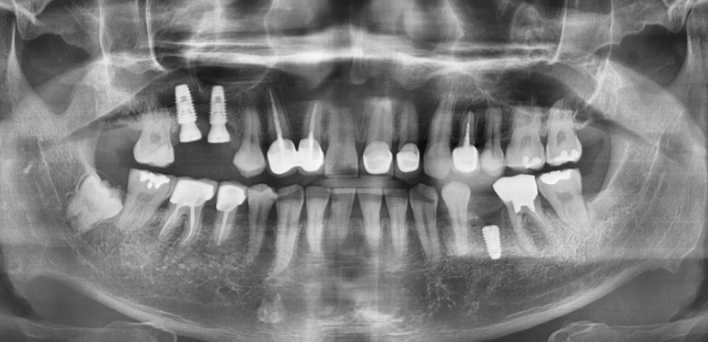

정확한 안모 맞춤형 분석

더서울치과의원은 개인의 얼굴과 가장 잘 어울리는 치아의 형태와 색상을 분석하고,

분석한 데이터를 기반으로 맞춤형 보철을 진행합니다.

더서울치과의원은 정확한 안모 분석을 통한 프로파일 예측 치료로 심미성은 물론 치아 본연의 기능 회복까지 가능하도록

안면 근육과 기능, 치아 형태, 비율, 크기, 교합, 색감 등 전반적인 비율을 맞추어 본인에게 잘 맞는 치아의 형태로 복원합니다.